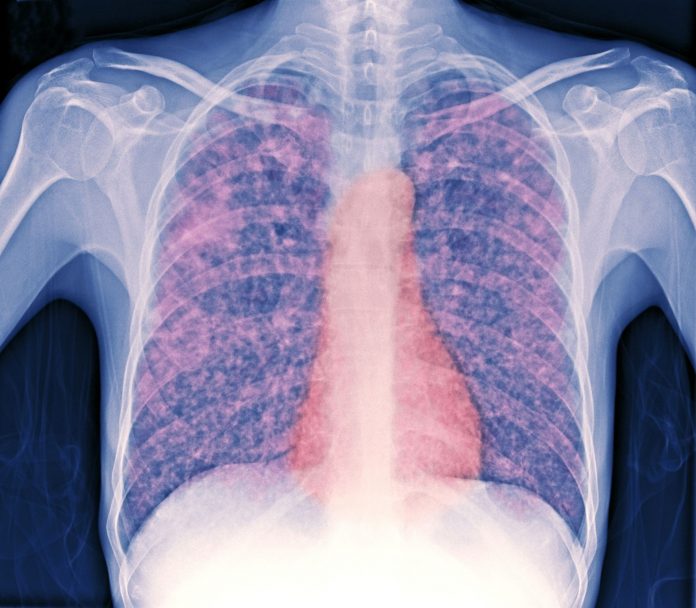

Recordaron que la tuberculosis es una enfermedad infecciosa y altamente contagiosa por el aire, especialmente cuando la persona enferma tose o estornuda sin tratamiento. Sus síntomas pueden incluir tos persistente, fiebre, pérdida de peso, sudoración nocturna, dolor torácico, e incluso sangre al toser en etapas avanzadas.